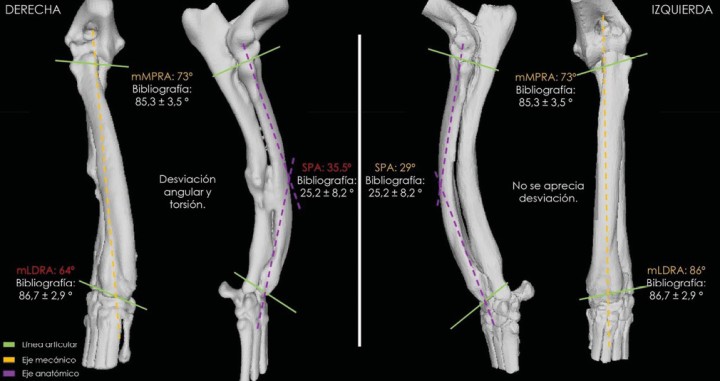

Estas mediciones angulares nos permiten comparar el radio afectado con uno estándar y cuantificar cuánto se desvía de los valores morfológicos. Además, es clave realizar dichas mediciones también en la extremidad contralateral (Fig. 1), porque, en caso de no presentar ninguna patología o síntomas clínicos, nos permite aproximar la corrección y respetar en la medida de lo posible la distribución simétrica de cargas.[ Fox DB, Tomlinson JL, Cook JL et al. Principles of uniapical and biapical radial deformity correction using dome osteotomies and the center of rotation of angulation methodology in dogs. Vet Surg 2006; 35(1): 67-77. [PubMed] , Dismukes DI, Fox DB, Tomlinson JL et al. Use of radiographic measures and three-dimensional computed tomographic imaging in surgical correction of an antebrachial deformity in a dog. J Am Vet Med Assoc 2008; 232(1): 68-73. [PubMed] , Knapp JL, Tomlinson JL, Fox DB. Classification of angular limb deformities affecting the canine radius and ulna using the center of rotation of angulation method. Vet Surg 2016; 45(3): 295-302. [PubMed] ]

Comparativa en 3D de ambas extremidades con la correspondiente deformidad.

Si se elucidan más ejes de los que suelen existir para el hueso en cuestión, la intersección de los ejes óseos correspondería al vértice de la deformidad (o deformidades), lo que da lugar a la identificación de un CORA. Por ejemplo, el radio canino posee un eje anatómico singular en el plano frontal. Si se examina un radio concreto utilizando el método CORA y se establece que posee dos ejes anatómicos en el plano frontal que se cruzan dentro de las corticales del hueso, entonces la intersección de los ejes definiría una deformidad singular y se consideraría una deformidad uniapical.[ Knapp JL, Tomlinson JL, Fox DB. Classification of angular limb deformities affecting the canine radius and ulna using the center of rotation of angulation method. Vet Surg 2016; 45(3): 295-302. [PubMed] ] En nuestro caso, el CORA quedó determinado por la intersección de dos ejes anatómicos (líneas rosas en Figs. 1 y 2). Por tanto, en este punto es donde se realizará el corte y posterior giro del fragmento distal para realinear cúbito y radio, es decir, el punto donde se efectuará la ostectomía en estos huesos que al haber quedado unidos se tratarán en bloque (Fig. 2).